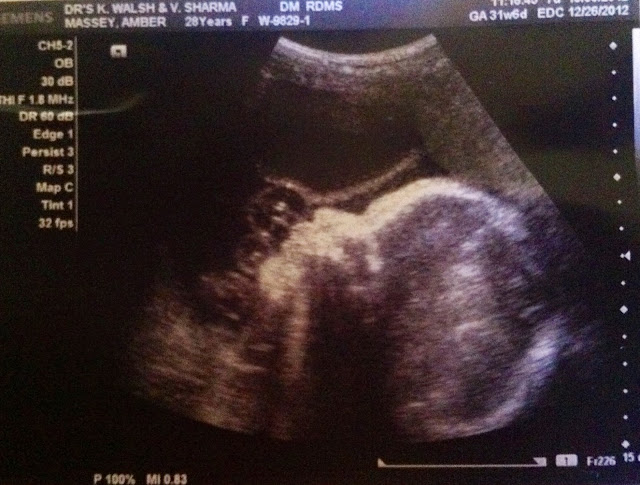

Jolie gave us a beautiful profile.. looking just so precious and getting bigger by the day!

Parker, however, was facing towards the sono screen and Dixie couldn't get her to roll over. She had the hiccups- which was so funny to actually see on the monitor. Both girls get them on a daily basis (Jolie more so than Parker), but seeing them react to hiccups makes it all pretty real. I've got little humans growing in there (duh..) Last week Parker had her back to the sono screen and we couldn't get a profile, and again this week she was uncooperative. Silly baby girl. You can see her lips, nose, eyes, and sweet little hand if you look carefully.